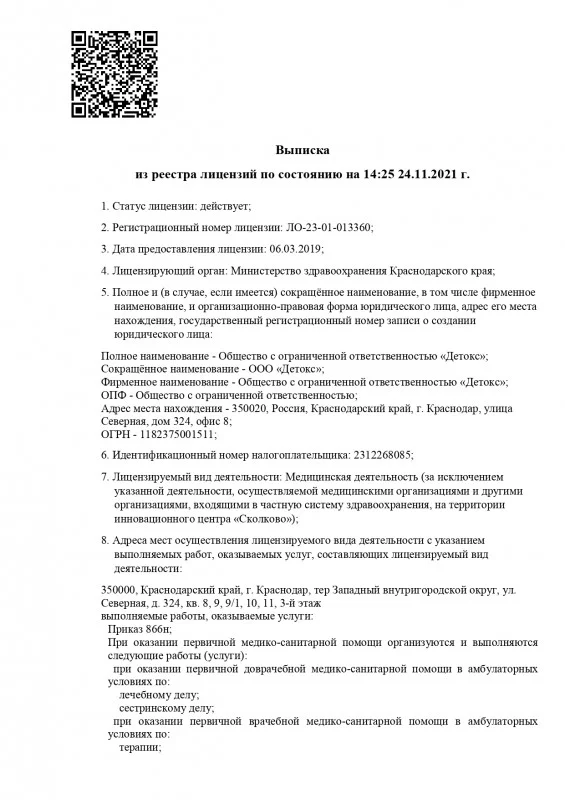

Лицензия на осуществление медицинской деятельности

Лицензия на осуществление медицинской деятельности

Лицензия на осуществление медицинской деятельности

Лицензия на осуществление медицинской деятельности

Лицензия на осуществление медицинской деятельности

Лицензия на осуществление медицинской деятельности

Лицензия на осуществление медицинской деятельности

Лицензия на осуществление медицинской деятельности